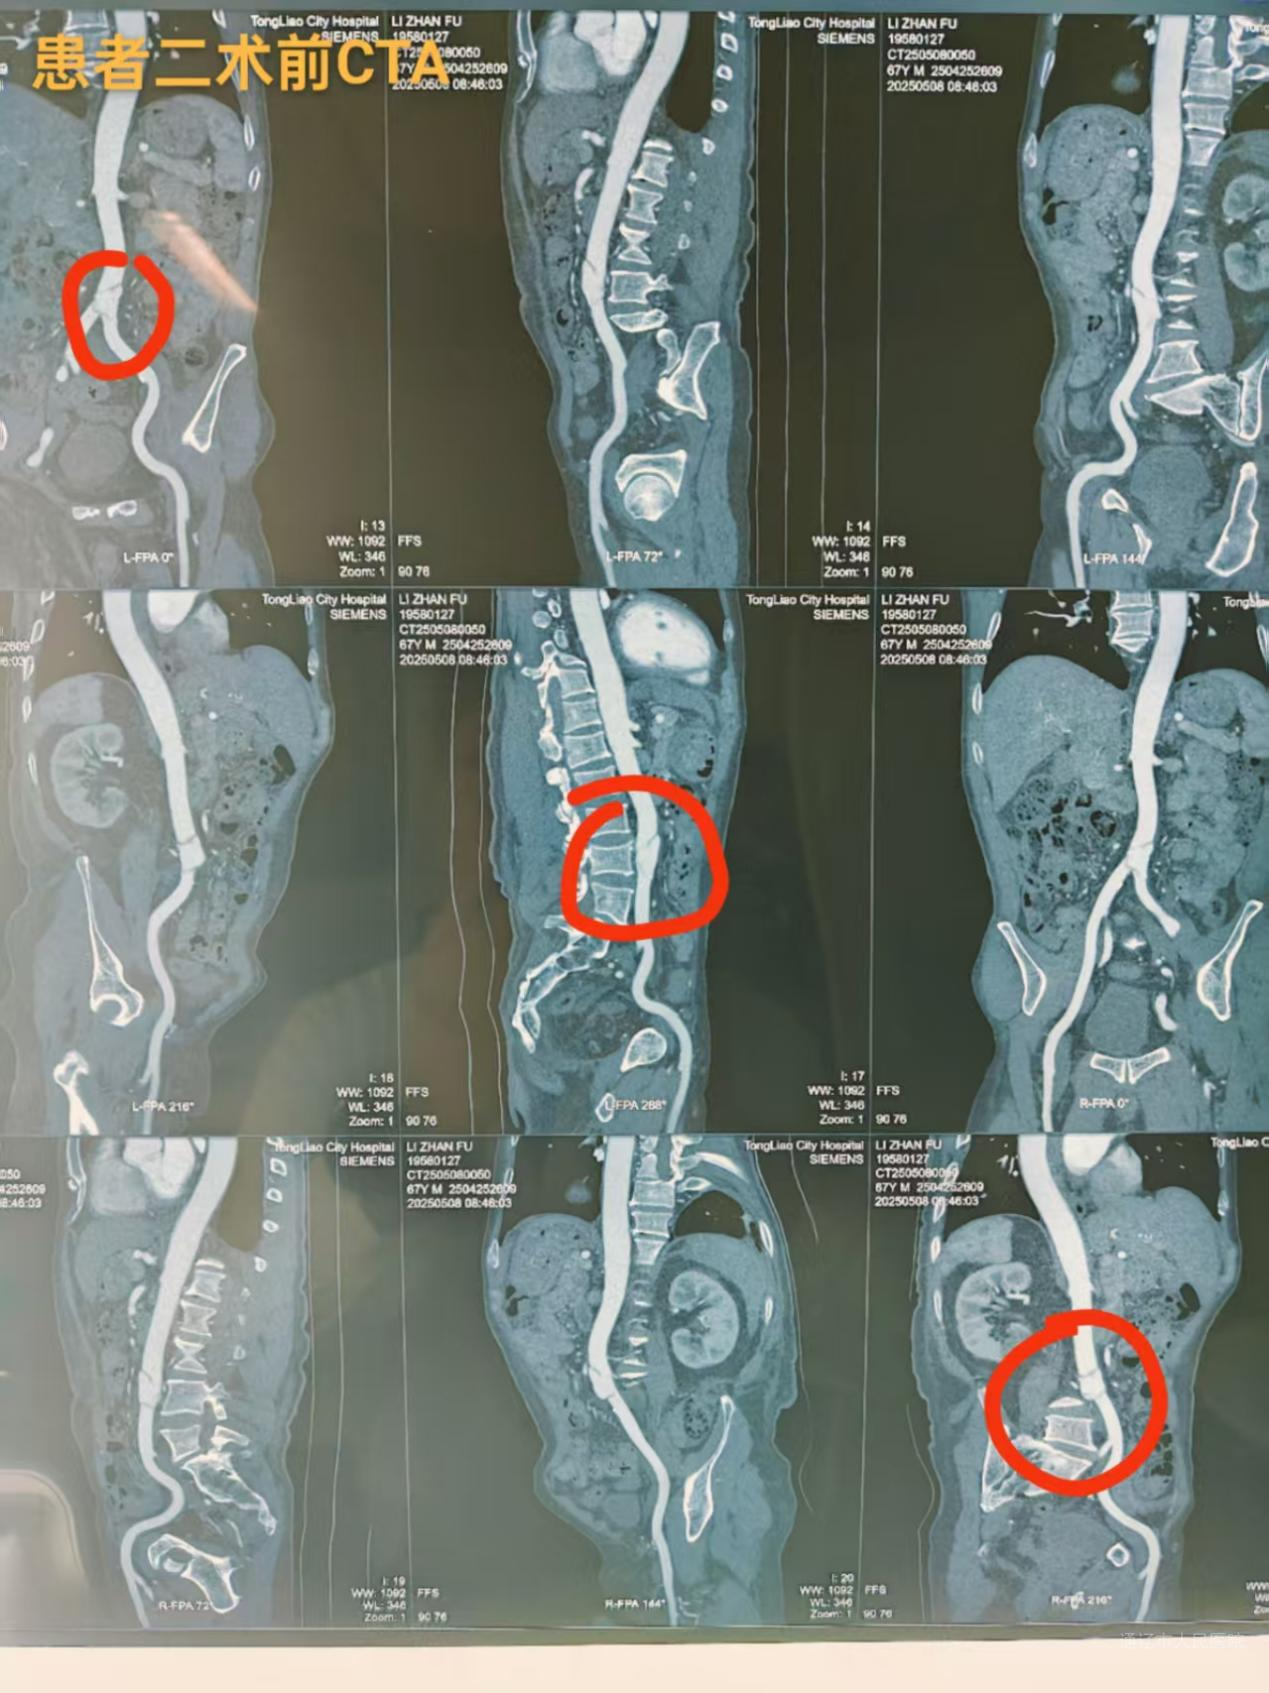

手术的成功离不开多学科团队的紧密协作与精准配合。血管肿瘤介入科与麻醉科、医学影像科、重症医学科等建立常态化协作机制,麻醉科创新采用“目标导向液体管理”维持血流稳定;医学影像科以高分辨率CTA和动态血流评估,为手术方案制定提供精准“路标”;重症医学科构建术后精细化监护体系,通过血流监测、脊髓灌注保护等措施降低并发症风险。各科室各司其职、协同作战,为患者的生命安全筑牢防线。

复杂胸主动脉瘤患者王某,因肺功能差被多家医院判定为开放手术禁忌症,血管肿瘤介入科团队仅通过双侧股动脉穿刺预制缝合器技术完成“胸主动脉瘤腔内修复术”,术后次日即可下地正常活动;腹主动脉夹层患者李某某发病时出现下肢缺血、尿量减少等器官灌注不足症状,经手术重建主动脉真腔后肢体温暖、尿量恢复。“没想到不用开刀就能治好这么严重的病,是介入技术给了我第二次生命!”两位患者康复出院时,难掩感激之情。